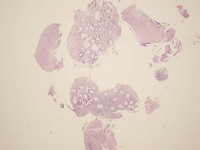

Figure 1: Colonic Biopsy H&E in Indolent T-cell Lymphoproliferative Disorder

These slides are from the second colonic biopsy. All three colonic biopsies revealed an almost similar morphology of a lymphoid infiltrate composed of medium sized lymphocytes expanding the lamina propria and displacing the crypts. There was no evidence of crypt invasion, cryptitis, or significant distortion of crypt architecture. The lymphoid cells had mature nuclear chromatin, inconspicuous nucleoli, and a moderate amount of eosinophilic to clear cytoplasm. Mitotic figures were hard to find, and an infiltrate of eosinophils also accompanied the lymphoid cells.